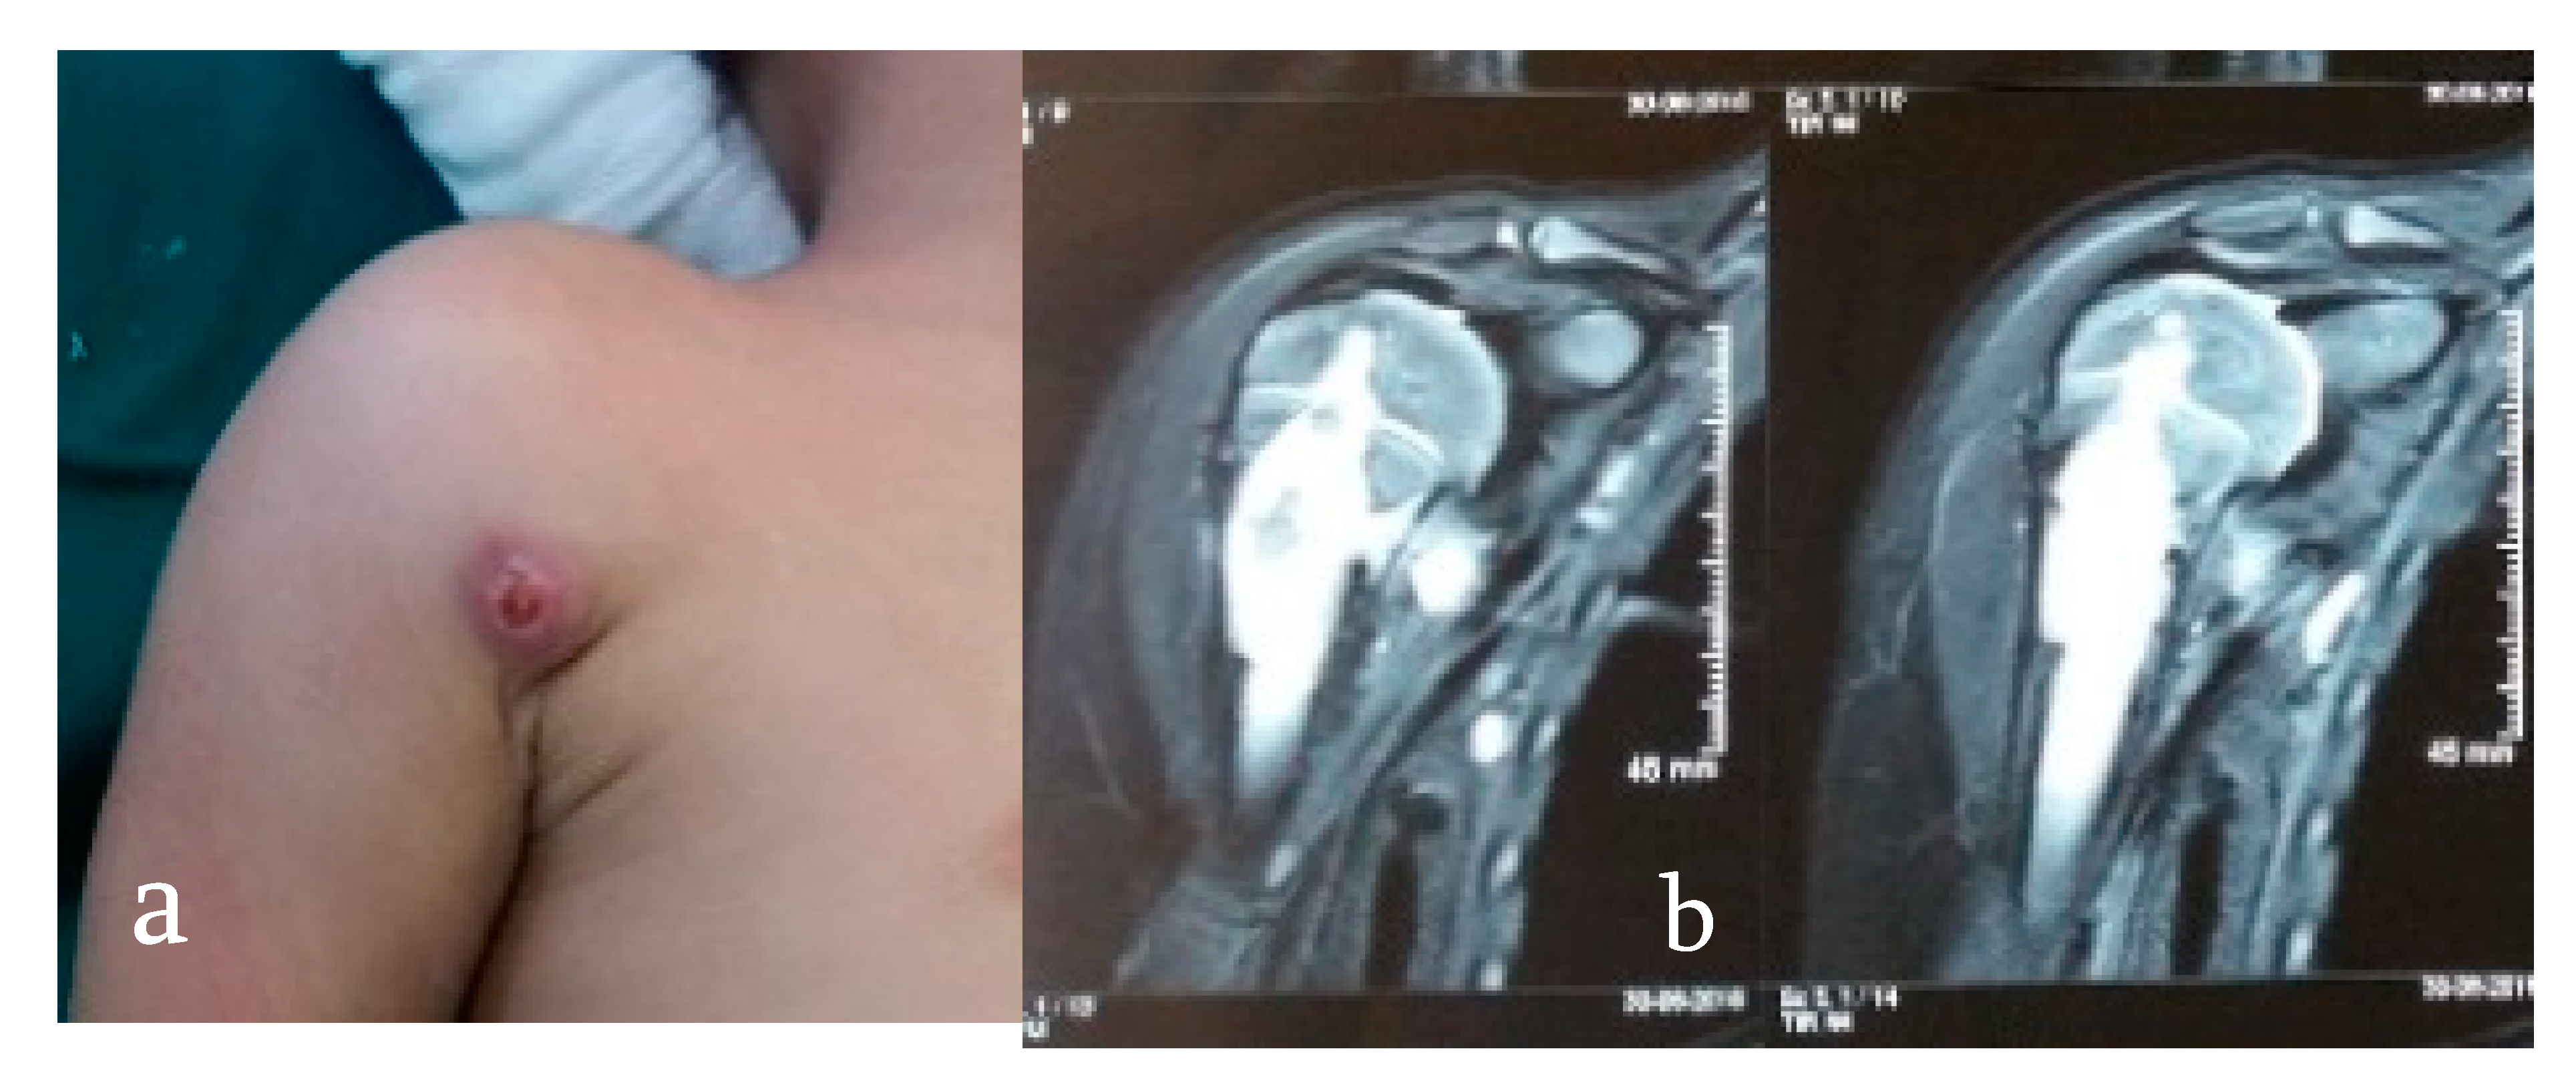

- Wagh, Y.; Reddy, R.; Gundavda, M.; Agarwal, M.; Agashe, V.M.; Bajwa, S. Tuberculosis (T.B.) masquerading as tumor. An 8-year study on 25 cases of long bone tuberculosis presenting as tumors. SICOT-J 2020, 6, 14. [Google Scholar] [CrossRef] [PubMed]